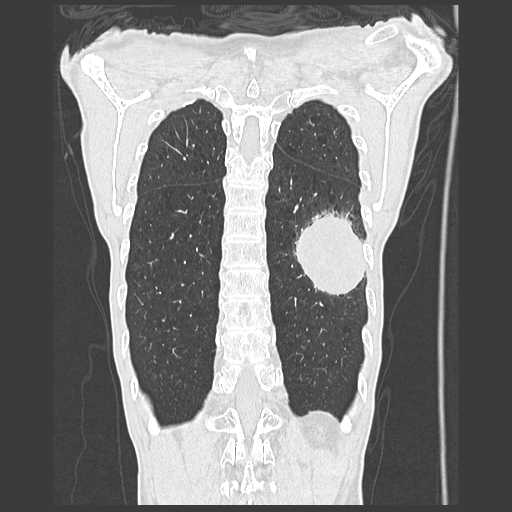

胸部

肺がん